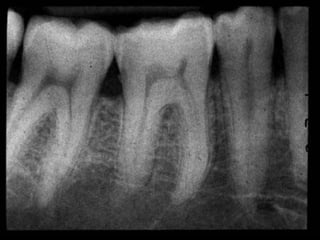

The normal pulp appear as radiolucent area

in the center of the tooth (radiolucency of

pulp because it contain no minerals within it).

• Radiographically the tooth show widening of

PDL space, in some patient the tooth may

show discontinuity in laminadura

• Widening of PDL space

• Discontinuity in lamina dura

• Thickening of lamina dura

• Condensing osteitis